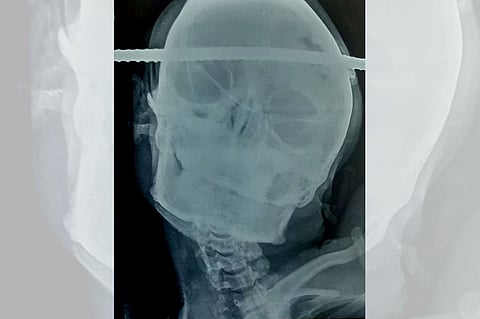

وتعود التفاصيل إلى سقوط سانجاي باهي البالغ من العمر 21 عامًا، أثناء عمله في بناء بئر يملكها، فتعرض لإصابة قاتلة بيده وجمجمته التي اخترقها قضيب حديدي ليمر من الجانب الأيمن إلى الجانب الأيسر، وفقًا لقناة «روسيا اليوم».

وأجرى فريق طبي جراحة للعامل الهندي بأحد المستشفيات، فيما فوجئ بأن المصاب ظل بكامل وعيه طوال الحادث، حتى إجراء العملية التي خضع لها لانتزاع القضيب الصدئ من رأسه؛ وذلك لمدة ساعة ونصف الساعة، فيما عانى الأطباء صعوبة بالغة في تخديره.

واستعرض جراح الأعصاب الدكتور برامود جيري تفاصيل الجراحة، مؤكدًا إجراءها بحذر شديد؛ ضمانًا لعدم تعرض مناطق الدماغ المحيطة بمكان الاختراق لضرر؛ حيث كان القضيب المعدني بعيدًا ملليمترات فقط عن الأوعية الدموية الرئيسية داخل منطقة مسؤولة عن نقل المعلومات بين الدماغ وأجزاء الجسم، وتحديدًا بين الرأس والعنق.